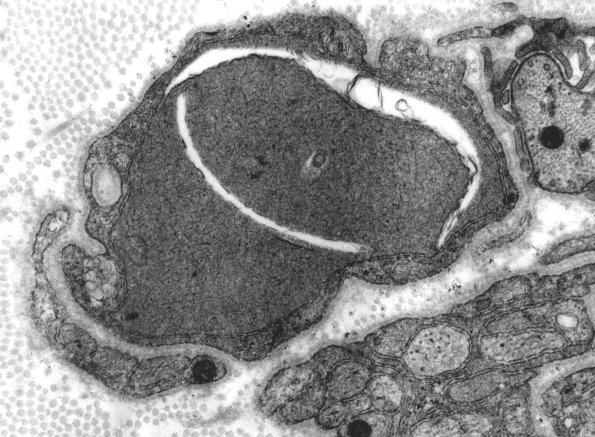

Case 4 No History ---- 4A An additional classical dystrophic axon with clefts and tubulovesicular elements. (electron micrograph)